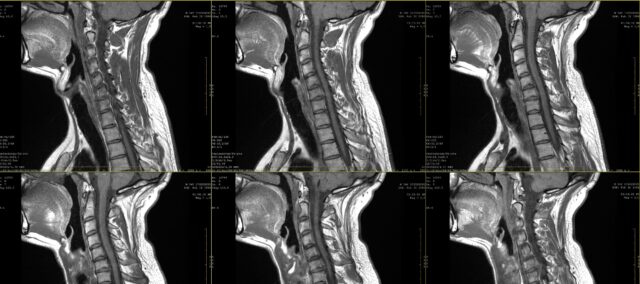

À l'école, vous avez sûrement appris les dessins de la douleur pour la douleur radiculaire. Toutefois, dès la première décennie du XXIe siècle, il est apparu clairement que la douleur radiculaire ne suivait pas nécessairement une distribution dermatomique. Cette étude visait à examiner de plus près la concordance entre l'inspection visuelle des dessins de douleurs radiculaires notés par les patients et l'IRM. En pratique, il arrive souvent qu'un patient exprime ses plaintes et que celles-ci soient complétées par un dessin de la douleur. Lorsqu'une douleur radiculaire est suspectée, une imagerie médicale est souvent prescrite pour déterminer la racine nerveuse affectée et l'étendue de l'atteinte possible de la racine nerveuse. Bien que cela fasse dans de nombreux cas partie de la pratique courante, nous ne savons pas tant que nous ne connaissons pas la concordance entre ces dessins de la douleur et la racine nerveuse affectée, telle que déterminée par IRM. Dans cette étude, Marco et al. (2023) ont comparé les dessins de douleurs radiculaires et les résultats de l'IRM.

Pour étudier la concordance entre les dessins de douleur radiculaire et les résultats de l'IRM, cette étude a inclus des participants ayant une histoire de deux mois de douleur persistante, qui ont été diagnostiqués avec une radiculopathie cervicale à l'IRM. Ce diagnostic a été posé par un neurochirurgien sur la base des informations cliniques et des résultats de l'IRM évalués par un radiologue.